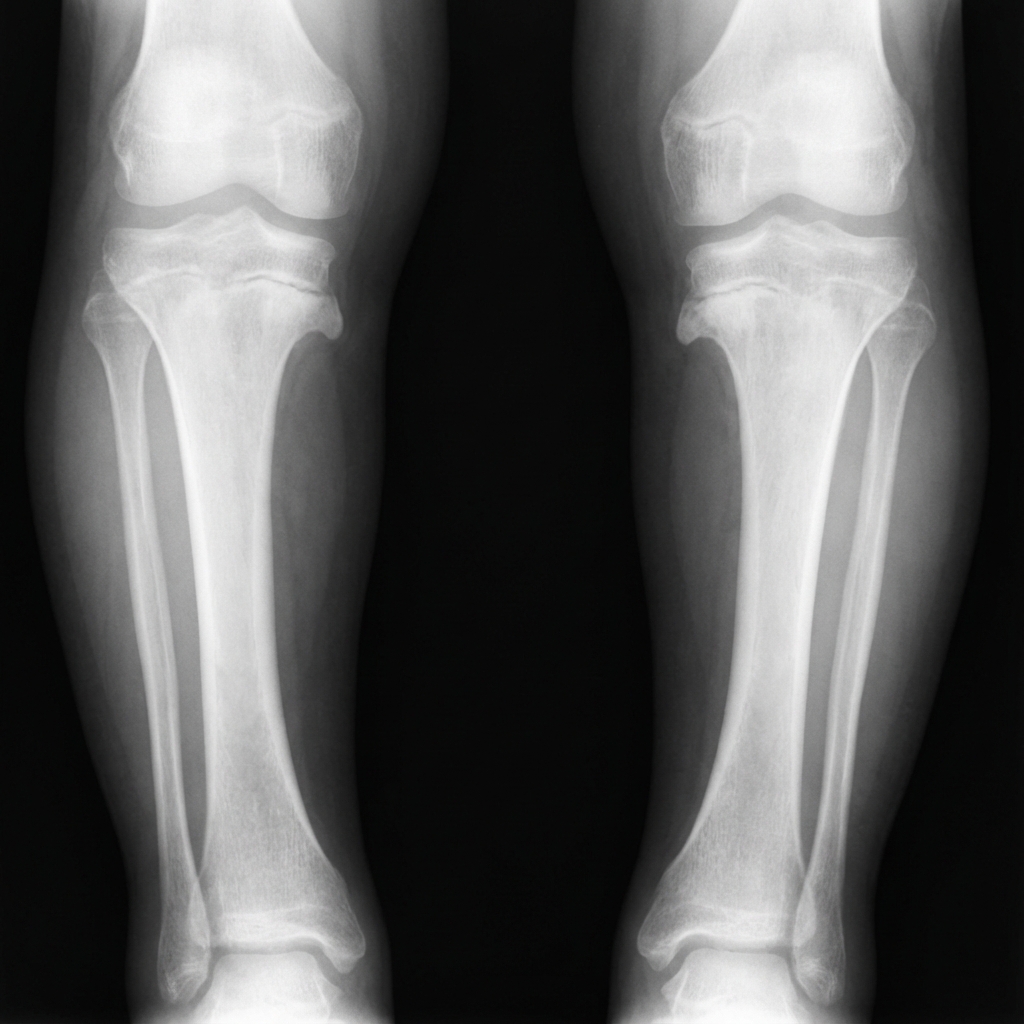

AP standing radiograph of the lower limbs in a 3-year-old child demonstrating bilateral Blount's disease. There is varus angulation of the proximal tibia bilaterally with characteristic medial physeal beaking. The metaphyseal-diaphyseal angle (MDA) is approximately 16 degrees on both sides (>11 degrees is abnormal). Langenskiöld Stage II changes are present with medial tibial metaphyseal beaking and early fragmentation. Internal tibial torsion is noted clinically.